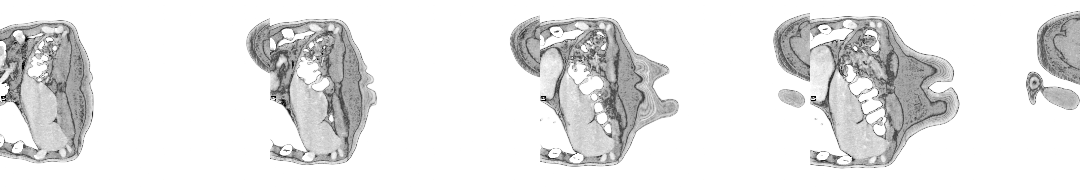

The moment I saw the very first scan the doctors showed me (bottom right, above: an MRI, rather than PET, as it happens)—on a small monitor wheeled into my cubicle at the Homerton—seemed to say everything at once. As I turned my head to look at the image of my brain on the monitor, I glimpsed also the tattoo on my left arm suddenly aligned with it (bottom left)—a tattoo of a bhikkhu meditating in flames, inked twenty years earlier, with the bhikkhu meditating as descibed in the Buddha’s Adittapariyaya Sutta (Fire Sermon)—such that the tattoo of the bhikkhu and the scan of the brain, aligned properly. One presaged the other by years, holding out its hand to the other. They reflected each other so neatly, with the tumour in the cerebellum showing up as the red-orange fire bursting through from within, which the bhikkhu sits through.

The wrinkled surface of the cerebral cortex in the scan echoed the Bhavachakra—the wheel of Saṃsāra, of cyclical existence (“Saṃsāra… is a Sanskrit word that means ‘wandering’ as well as ‘world’, wherein the term connotes ‘cyclic change’ or, less formally, ‘running around in circles’)10—against which the bhikkhu rests in the tattoo. Here is an image, not only of that empty time turning that we have talked of, of cyclical return and, dare I say it, reincarnation (though in this formulation, reincarnation is mere repetition, as in the ‘natural’ repetition of pagan society). In the original Fire Sermon, the argument is that the bhikkhu must free themself from the grasping tyranny of the senses. We, on the other hand, will be moving in the other direction. In any case, this combined image almost made me fall out of bed.